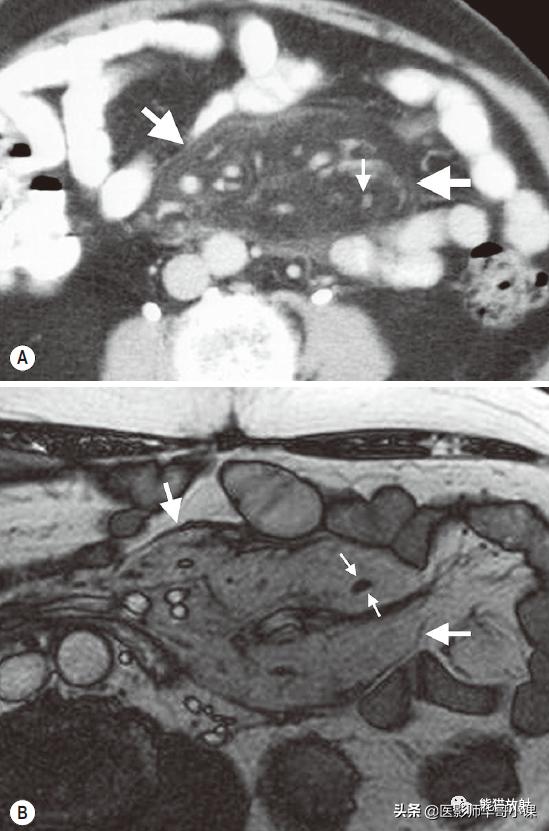

肠系膜脂膜炎的特征性CT表现 为肠系膜根部边界清晰、密度不均的脂肪肿块,包绕肠系膜血管,可推移或不推移邻近肠襻,但不侵犯邻近肠襻,血管周围可见低密度环(图)。T2WI上呈低信号包膜,静脉注射对比剂后可见强化。

回缩性肠系膜炎CT表现 为浸润性软组织密度肿块,周围可见放射状条索影(图),这些特点可能与纤维瘤病或类癌相似。 硬化性肠系膜炎 在T1WI和T2WI图像上均呈低信号,有助于疾病的鉴别。肿块中央坏死区可见钙化(图)。该病有一定的自限性,通常预后较好。

肠系膜脂膜炎。患者腹痛,增强CT(A)和真实稳态进动快速成像(true-FISP) MRI(B) 显示一个边界清晰的脂质肿块(大箭),从小肠系膜根部向左侧腹部延伸,包绕肠系膜血管,无扭转。注意血管周围的晕环(小箭)

纤维性肠系膜炎。不明原因发热患者,增强CT显示边缘不规则纤维脂肪样肠系膜肿块包绕肠系膜血管。从肿块到相邻的肠系膜脂肪可见放射状软组织条索影。

纤维性肠系膜炎。CT表现增强CT显示大而边界模糊、广泛钙化的肠系膜软组织肿块。注意邻近的肠襻回缩及增厚。